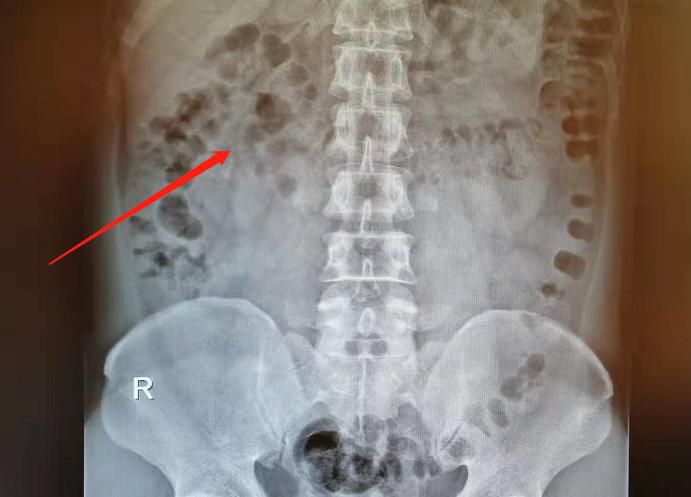

△體外碎石前。

△體外碎石後。